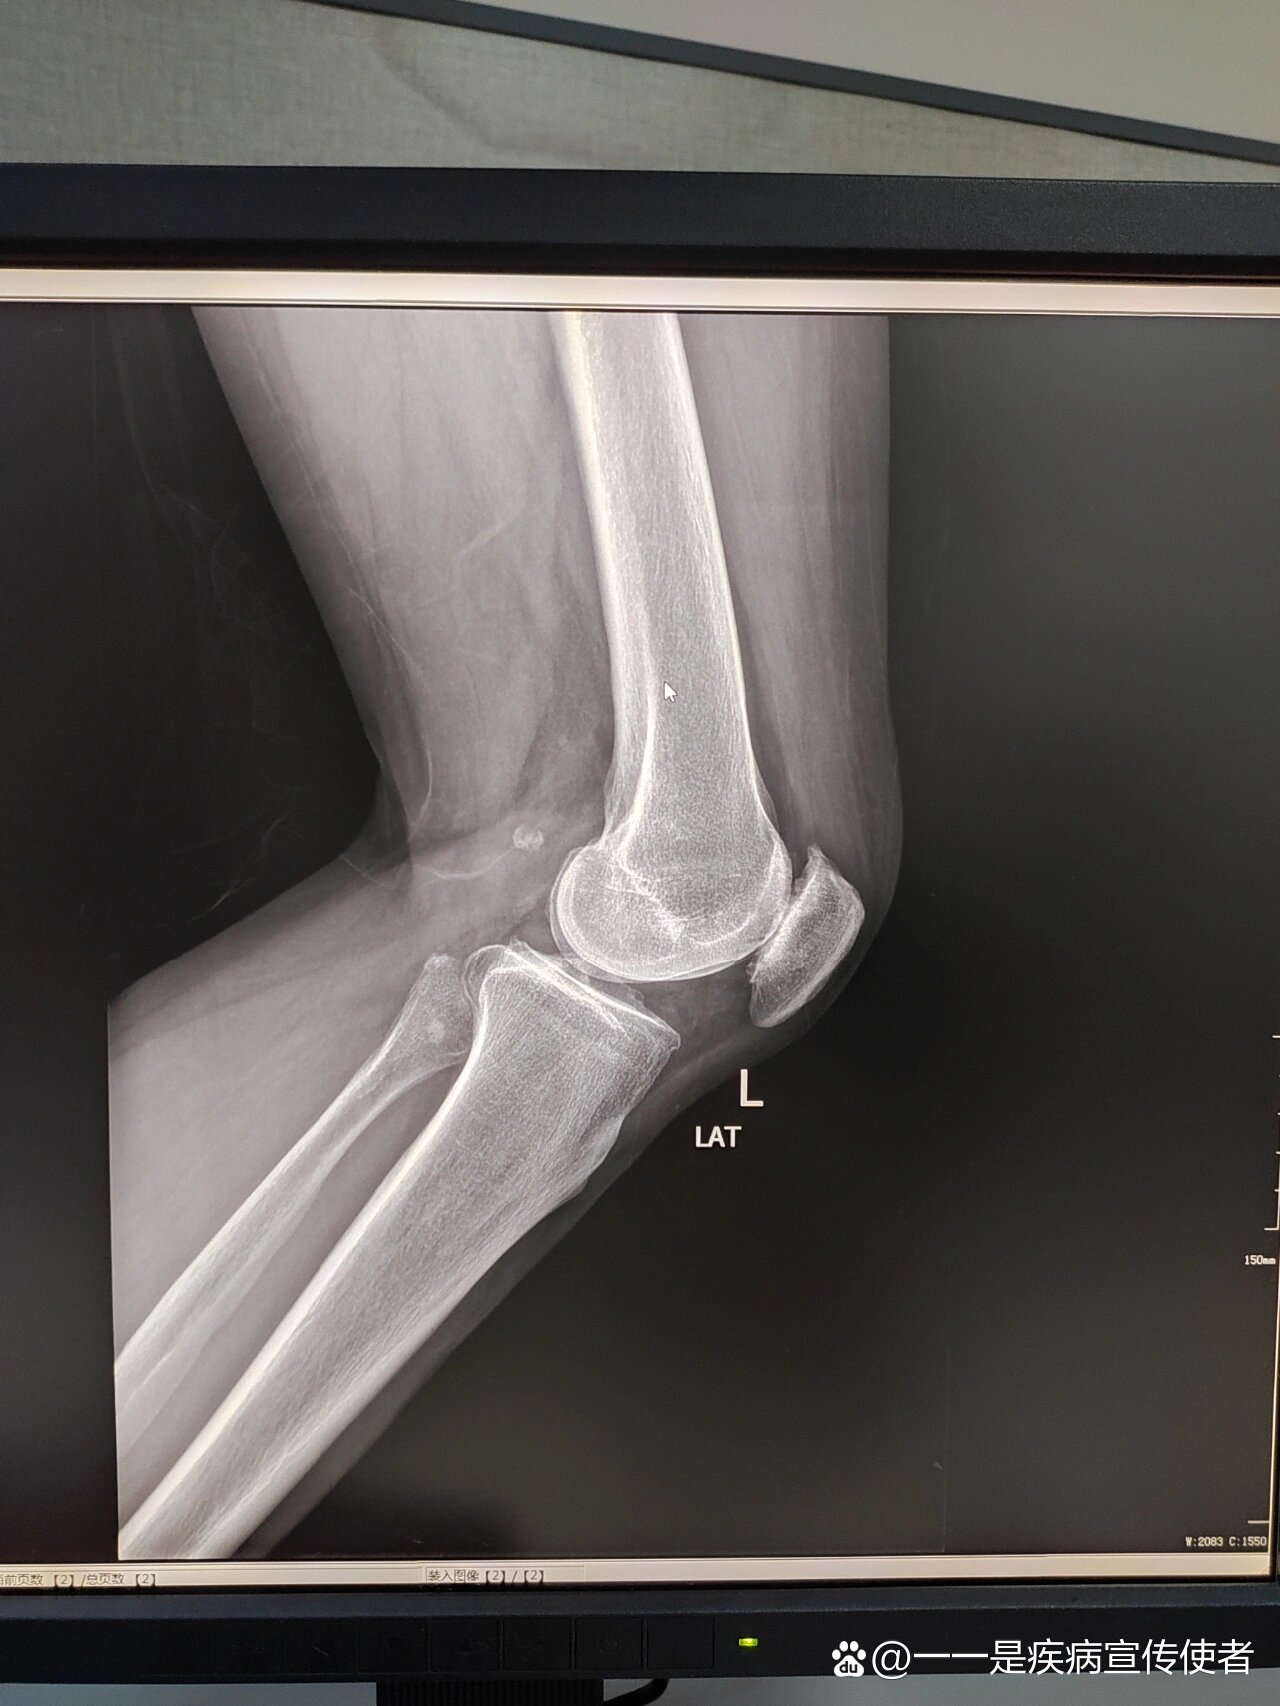

57楼回复老住院医师2008-06-12 00:00:07女性,18y,因车祸致左膝关节

左膝关节正侧位片一例,请各位老师看一下.

左膝关节正侧位 - 影像医学和核医学讨论版 -丁香园论坛

郝某,女,15岁,左股骨远端骨折术后膝关节强直